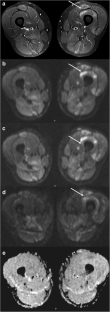

Fig. 4